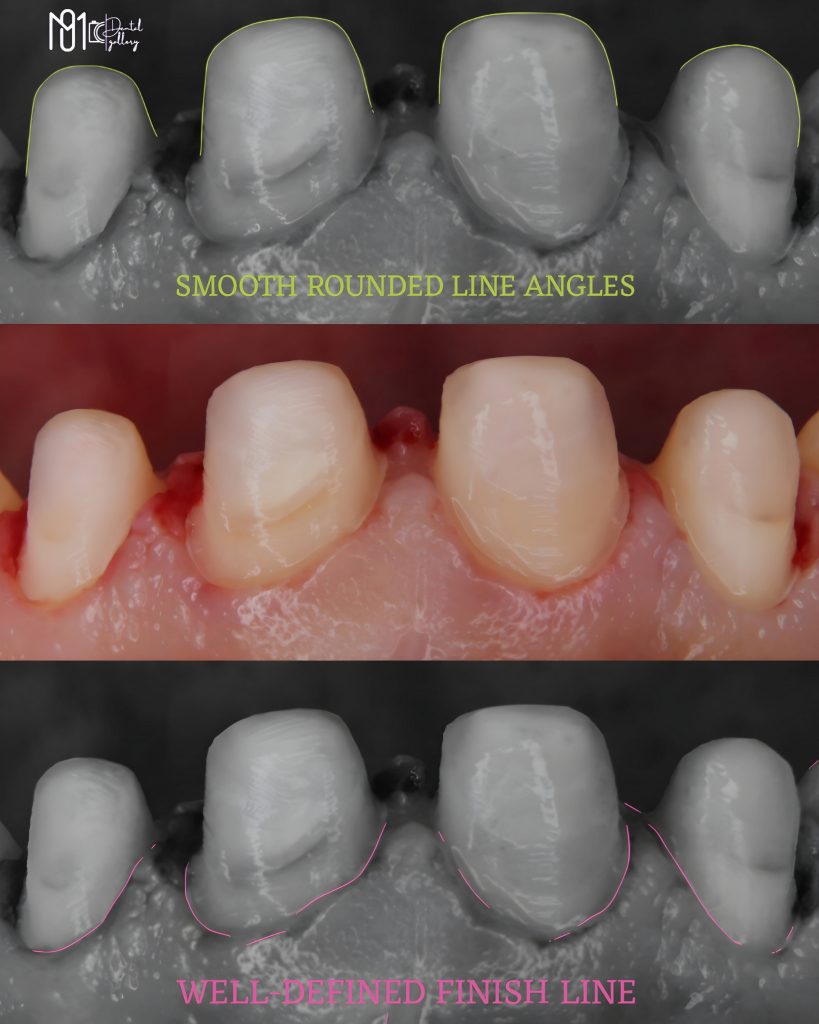

The case involved managing extensive carious lesions across both arches, performing root canal treatments, direct and indirect restorations, and even a periodontal surgical procedure.

I treated multiple deep caries cases using Immediate Dentin Sealing (IDS), performed Composite Resin Restorations (CRR) for both anterior and posterior teeth, and placed temporary restorations to maintain occlusion before the final prostheses.

This case involved almost every aspect of dentistry — diagnosis, endodontics, restorative, prosthodontics, and periodontal surgery — and I couldn’t be prouder of how far I’ve come through it.